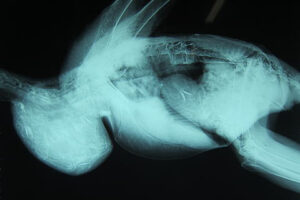

レントゲン検査でも

レントゲンを撮ってみると、案の定。そのうの中に何やら細かなものがギッシリと詰まっています。上のレントゲン写真は、ワシの頭(レントゲンには写ってません)が画像の左側、尾が右側になるように、身体を左横から撮影したものです。